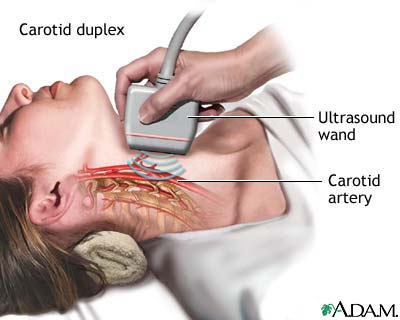

- Arteries in the neck

- Veins or arteries in the arms, legs, or abdomen